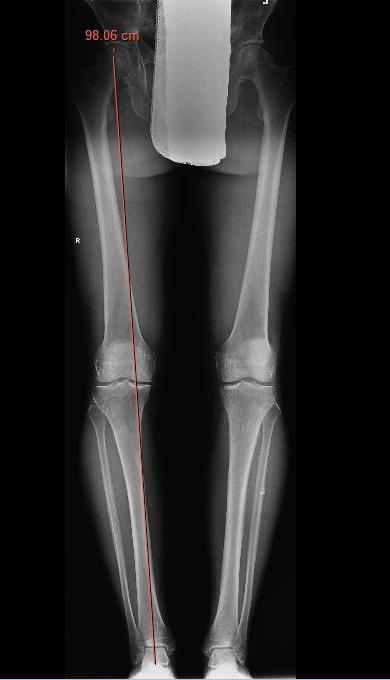

Check correct alignment with drop rod

- goal lateral tibial spine

- Fujisawa point / 62% of the tibial plateau / lateral tibial spine